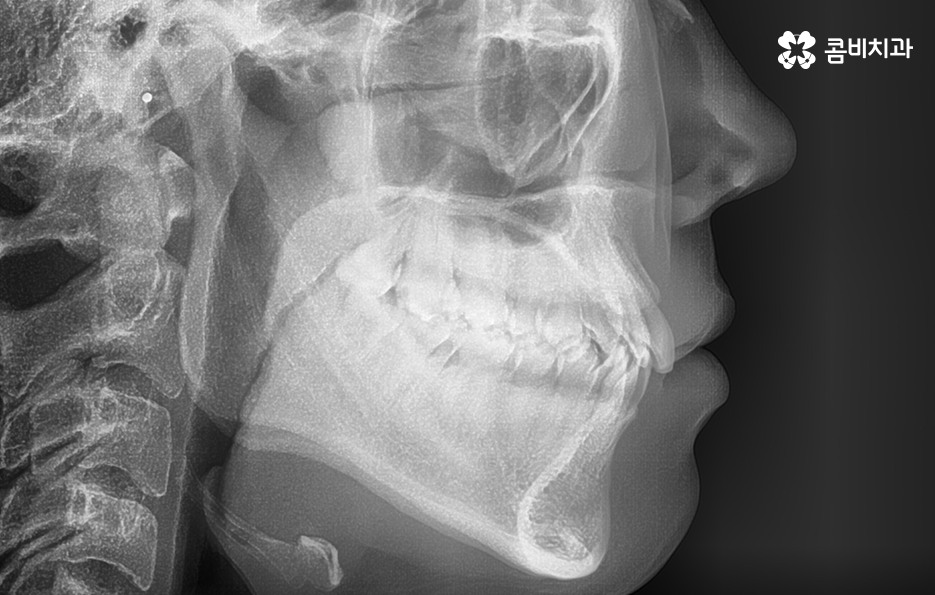

교정에 대해 알아보시면 단순히 치열을 가지런하게 재배열 혹은 펴는 개념만이 아니라 치아교정을 통해 부정교합을 치료하여 치아의 기능적인 부분을 개선하거나 얼굴 변화에 대한 부분, 치아의 건강 등 종합적으로 알아봐야 할 점들이 많다는 것을 알 수 있는데요.

이 중에서는 발치 여부에 대해서도 많은 고민이 되는 부분 중에 하나일 거예요. 교정 치료에서 발치를 하는 경우에는 보통 작은 어금니를 발치하여 치아의 이동 공간을 확보하는 경우가 많은데 아무래도 생니를 발치한다는 생각에 발치는 무조건 안좋다고 느끼거나 거부감을 느끼시는 분들도 많이 있어요.

교정 치료는 크게 발치와 비발치치아교정으로 나뉠 수 있는데 비발치치아교정의 경우에는 아무래도 치아가 움직이는 양도 적고 그에 따라 교정 기간도 짧은 편에 해당되고 있어요.

그렇기 때문에 비발치치아교정이 좋다고 생각하기 보다는 개인에 따라서는 치아의 이동 공간 확보를 충분히 하기 위해 발치가 필요한 경우도 있고 얼굴 변화나 부정교합의 개선을 위해 발치가 필수적인 경우도 있을 거예요

단순히 비발치치아교정이 발치를 안해도 되니 무조건 좋다고 판단하기 보다는 각 개인의 치료 목적과 구강 및 골격, 얼굴형의 상태를 종합적으로 정밀 검진하여 자신에게 적합한 치료 계획을 잘 세우는 것이 중요하다고 강조드리고 있어요